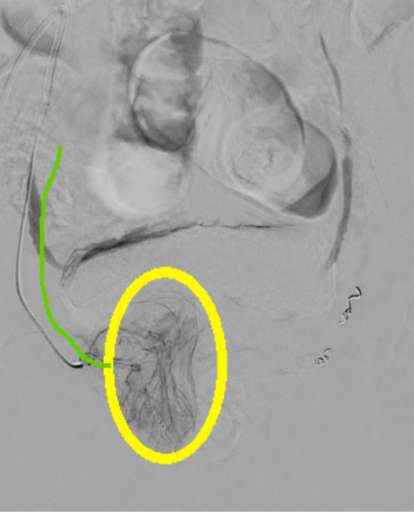

להלן תמונות נבחרות מתוך הצנתור.

הזרקת חומר ניגוד בעורק הכסל הפנימי הימני.

אפשר לראות את המעקף (מסומן בצבע אדום) המוביל דם לערמונית מימין ובהמשכו באמצעות מעקף לעורק הערמונית השמאלי (מסומן בסגול). גבולות הערמונית מסומנות בצהוב. מיקרוקטטר בירוק.